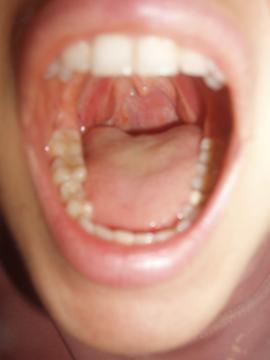

Pro větší náhled klikněte na obrázek

Dobrý den,nedávno mě bolelo v krku, ale už se cítím dobře, jenže se mi nezdají mandle, připadají mě nateklejší..nikdy jsem si pusu nezkoumala, tak vlastně nevím, jestli je to v pořádku. K doktorce se jít nechystám, měla jsem ATB nedávno, a raději se vyléčím přírodní cestou. Moc děkuji za odpověď

Nevidím na mandlích nic špatného, nicméně z fotografie nelze příliš soudit. Doporučuji navštívit lékaře.